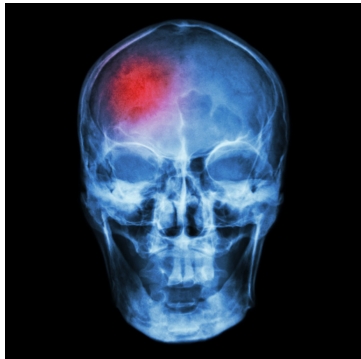

discuss the anatomy and function of the brain and which body parts the

different areas control,” she continued. “For example, the frontal lobe

controls motor functions, higher order functions, planning, reasoning,

judgment, impulse control, memory and personality. We discuss how the

brain is irreplaceable, cannot be mended like a broken bone, and there

is no cure for a TBI. It only takes a split second to change your life

forever.”

The

BIAA offers vast information about the effects of brain injuries and

the effects that are correlated with the side of the brain that was

injured. For example, injuries on the left side of the brain can cause

difficulties understanding and speaking language, depression, anxiety,

impaired logic and decreased control over right-sided body movements.

Rightsided injuries can cause altered creativity and music perception,

loss of “the big picture” type of thinking, and decreased control over

left-sided body movements. Injuries that are scattered throughout both

sides may cause reduced thinking speed, confusion and impaired cognitive

thinking skills – among other effects.